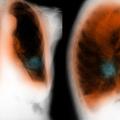

Pogosti vzrok smrti Ta bolezen je neozdravljiva, kako vem, da jo imam KOPB je tretji najpogostejši vzrok smrti na svetu.

Večina zanjo ne ve Bolezen je neozdravljiva, njenega napredovanja ni možno ustaviti Večina to bolezen odkrije šele v poznih stadijih, zaradi česar jo Svetovna zdravstvena organizacija po umrljivosti uvrš…

Zdravje Opozorilo: Približno eden od desetih zaradi tega tudi umre Prepozno odkrita bolezen: Vseh bolnikov s KOPB je v Sloveniji med 50.000 in 100.000. Izmerite si pljučno funkcijo.

Zdravje Opozorilo: Približno eden od desetih zaradi tega tudi umre Strokovnjaki še opozarjajo, da se večina bolnikov s KOPB tega ne zaveda.

Do 100 tisoč bolnik… Bolezen, ki jo mnogi pripisujejo staranju, čeprav to ne drži Strokovnjaki opozarjajo, da se nastale škode ne da popolnoma popraviti, vendar se da bolniku pomagati.